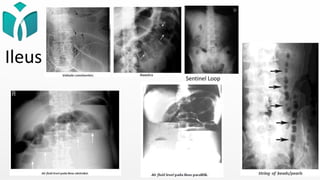

Ileus Obstruktif vs Paralisis

Ileus Obstruktif Ileus Paralisis

Distensi Proksimal tersumbat Semua bagian usus

Udara Distal dari titik obstruksi Di seluruh usus

Manifestasi Klinis Nyeri abdomen, muntah, distensi, konstipasi,

awal gejala  bising usus meningkat u/

mengeluarkan isi sumbatan

Kembung, mual, muntah,

konstipasi, bising usus berkurang

sampai hilang, nyeri menyeluruh,

DM (+), distensi gaster – colon

Peritonitis Jarang Berhubungan

Preperitoneal Fat (+) (-)

Gambaran

Radiologis

• Air fluid level pendek-pendek (+)  Step

Ladder appearance

• Dilatasi dinding usus di proksimal obstruksi

• Pada letak tinggi: valvula conniventes

terlihat jelas (+), string of pearls (+)

• Letak rendah: haustra terlihat jelas (+)

• Sentinel loop

• Herring bone appearance

• Air fluid level memanjang (+)

• Dinding usus menebal

Ileus

Sentinel Loop